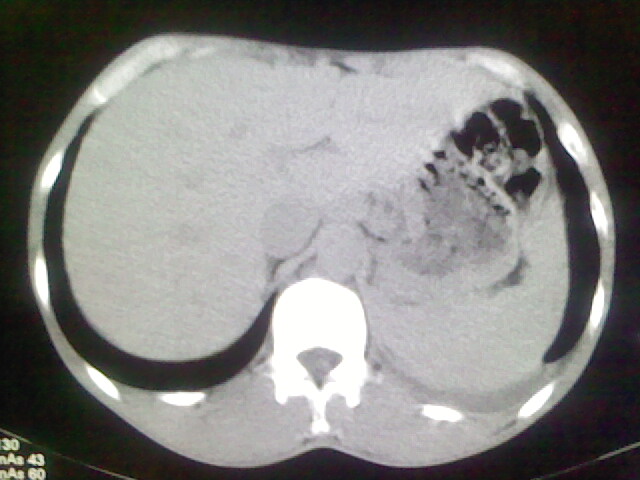

以下是引用杀毒软件在2008-9-3 6:11:00的发言:[br]侵袭性胸腺瘤------一般不侵到气管旁[br][br]考虑----纵隔淋巴瘤,心包及胸膜受累

以下是引用随光逐影在2008-9-3 7:07:00的发言:[br]1)考虑淋巴瘤可能。2)双侧胸腔积液(以左侧为甚)。3)心包积液。